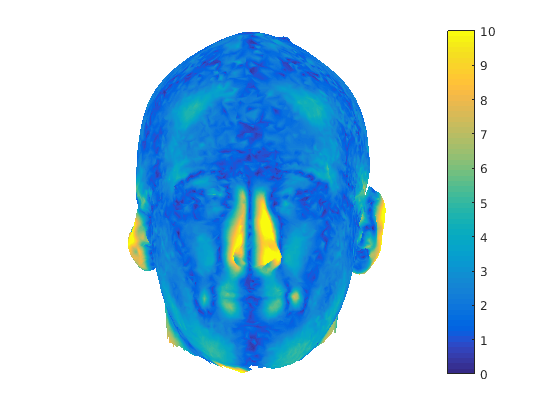

The region that the head scan and its reflection lie in is pre-partitioned into cuboid bins to reduce the computational cost of nearest neighbour search. Fig. 11 show the results of global symmetry plane alignment for 8 adult male samples from the headspace dataset. From observing 100 of these scans we have noticed that the nose, a cartilaginous structure, is often not aligned with the global symmetry plane and regions around the nose area are often rejected as outliers in the trimmed ICP process. As a result, it is not possible to build a good profile model of the face using global symmetry alone, as the ridge of the nose is often not sufficiently well aligned with the global symmetry plane. This motivated us to find the facial contour using local symmetry considerations.

In order to find the facial contour we implemented a piecewise ICP process across the glocal symmetry plane. Each head is first rotated such that its global symmetry plane is coincident with the Y-Z plane. The facial region, as defined by the sparse model fit is then divided into a set of horizontal strips (we use 20mm steps between the nasion and pognion) in the dimension, with the back of the head being cropped out. We apply our trimmed ICP algorithm to each separate strip, so that a local symmetry plane is found for each strip and the facial contour is found by intersecting this sequence of local symmetry planes with its corresponding facial strip. For each strip (index ), we use the strip below and the strip above in the trimmed ICP process in order to reduce the sensitivity of the local symmetry planes to noise. This process is only applied to the face and the cranial region is dealt with as a whole. This is because, in strips, it does not provide sufficient constraints for ICP to lock onto and the two surfaces can slide over each other freely. Fig. 12 shows facial local symmetry contours deviating from the global symmetry plane. Points on the head profile are then extracted by detecting mesh arcs that cross a symmetry plane and linearly interpolating to extract 3D vertices that lie on that symmetry plane.